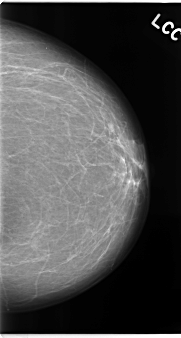

C_0121_1.LEFT_CC

LEFT_CC LINES 4728 PIXELS_PER_LINE 2528 BITS_PER_PIXEL 12 RESOLUTION 50 NON_OVERLAY